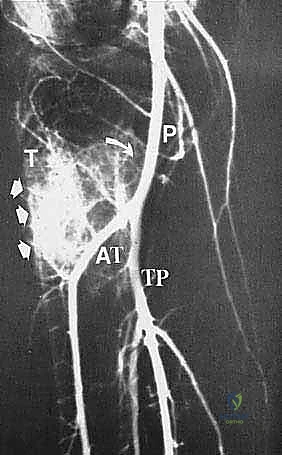

يُعد الشريان المأبضي (Popliteal Artery) بمثابة شريان الحياة الرئيسي للطرف السفلي. يمر هذا الشريان الضخم خلف مفصل الركبة مباشرة في منطقة تُعرف بالحفرة المأبضية (Popliteal Fossa). عند وصوله إلى الحافة السفلية للعضلة المأبضية، يتفرع هذا الشريان إلى شبكة معقدة تُعرف باسم "التشعب المأبضي ثلاثي الفروع" (Trifurcation)، وهي تتكون من:

- الشريان الظنبوبي الأمامي (Anterior Tibial Artery): وهو أول فرع ينشأ من الشريان المأبضي، ويتجه للأمام ليغذي الجزء الأمامي من الساق.

- الجذع الظنبوبي الشظوي (Tibioperoneal Trunk): وهو استمرار للشريان المأبضي بعد تفرع الشريان الأمامي.

- الشريان الشظوي (Peroneal Artery) والشريان الظنبوبي الخلفي (Posterior Tibial Artery): وهما يتفرعان من الجذع الظنبوبي الشظوي لتغذية الأجزاء الجانبية والخلفية من الساق والقدم.

يُعد الفهم العميق والدقيق لهذه التفرعات أمراً بالغ الأهمية ويفصل بين نجاح الجراحة أو فشلها الكارثي. أثناء عملية استئصال الورم من الظنبوب القريب، غالباً ما يضطر الجراح إلى التعامل بحذر شديد مع هذه الأوعية. في بعض الحالات، يتطلب الأمر ربط (Ligation) الشريان الظنبوبي الأمامي إذا كان الورم قريباً جداً منه، مع ضرورة تحديد وحماية الأوعية الأخرى (خاصة الشريان الظنبوبي الخلفي) لضمان استمرار إمداد الدم الكافي للساق والقدم بعد الجراحة، وتجنب خطر تموت الأنسجة (Ischemia). هنا تبرز أهمية مهارات الجراحة المجهرية التي يتقنها الأستاذ الدكتور محمد هطيف لضمان سلامة هذه الأوعية الدقيقة.